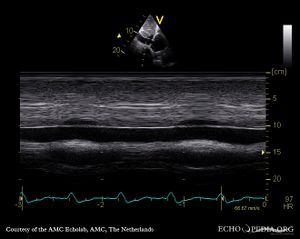

مخطط صدى القلب

يتم عمل تحليل ميتا عن طريق صدى الصوت الناتج عن تأثير دوبلر للتنبؤ بالقسطرة، هذا يعطي حساسية بنسبة 88% وفعالية بنسبة 56%.[14]

4 month old with pulmonary hypertension as seen on ultrasound[15]